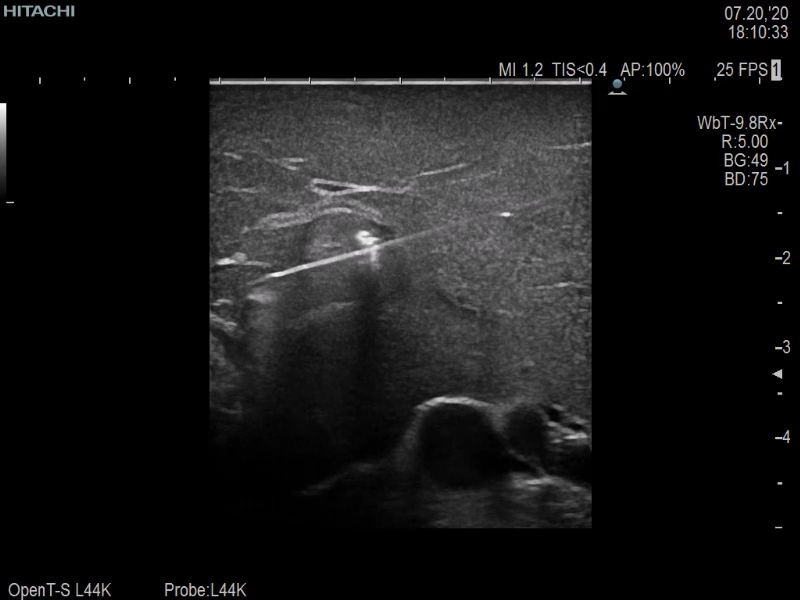

Giving the surgeon complete control

The Fujifilm Healthcare transducer utilizes the full benefits of the Wrist Articulation™ of the robotic instruments to capture real-time ultrasound imaging even at complex angles and difficult-to-reach areas.

Our smallest footprint allows for enhanced contact in tight spaces

Our newest probe, the L51K allows the surgeon access to difficult-to-reach areas that no other probe on the market can go. The unique design and proximal location of the attaching mechanism provides full wrist articulation and easier grasp and release.

The next level in Robotic Ultrasound

Full wrist articulation with optimized functional length.

A critical function of robotic ultrasound guidance is tumor margin identification. Fujifilm's family of robotic probes all have the optimum location of the attaching mechanism that allows for full wrist articulation of the probe. The result is an increased confidence that the tumor margins have been completely identified.